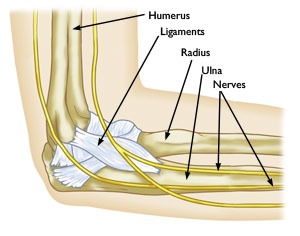

AnatomyYour elbow joint is a joint made up of three bones: your upper arm bone (humerus) and the two bones in your forearm (radius and ulna). Muscles, ligaments, and tendons hold the elbow joint together.

The elbow is a combination hinge and pivot joint. The hinge part of the joint lets the arm bend like the hinge of a door; the pivot part lets the lower arm twist and rotate. Several muscles, nerves, and tendons (connective tissues between muscles and bones) cross at the elbow.